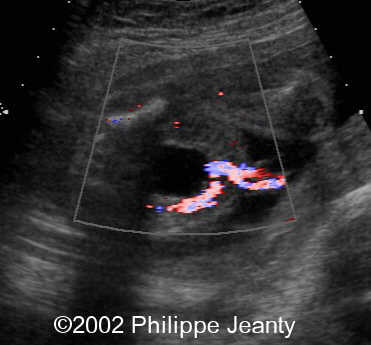

Ultrasound appearance

A transverse section of the umbilical cord shows two vessels. Examination of umbilical blood flow with color Doppler may facilitate diagnosis. However, by far the easiest way to assess the number of arteries, is by identifying the intra-abdominal portion of the umbilical artery along side the bladder with color Doppler17,18.